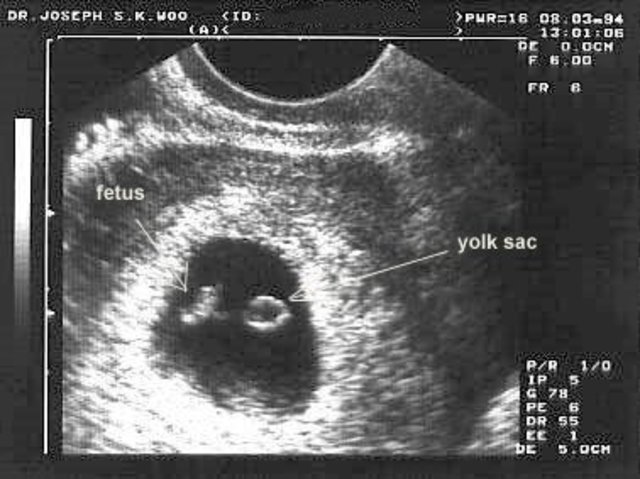

The heart is beating around 150 beats per minute as the face begins to take shape. Limbs are still growing while eyes are developing.

The heart is starting to beat . The brain, blood vessles and the spinal cord are begining to form.

The heart is beating with one chamber while organs are begining to grow. The legs and arms are growing and looking like paddles.